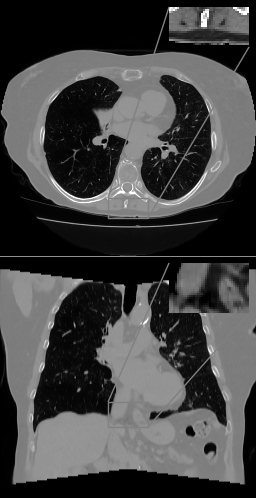

Refer to caption

(a)

(b)

Figure 5: (a) Axial (top) and coronal (bottom) slices of pelvic TV++ reconstruction, HU range=(-400, 400) and (-150, 250) for ROI, (b) LIRE++

In order to demonstrate that LIRE++ can be scaled to full resolution, we provide sample reconstructions with 1 mm voxel pitch in Figure 5 from the extended version of LIRE++ and compare them to TV++ reconstructions. The reconstructions from LIRE++ are less noisy; however, more finetuning might be needed to completely remove image artifacts.